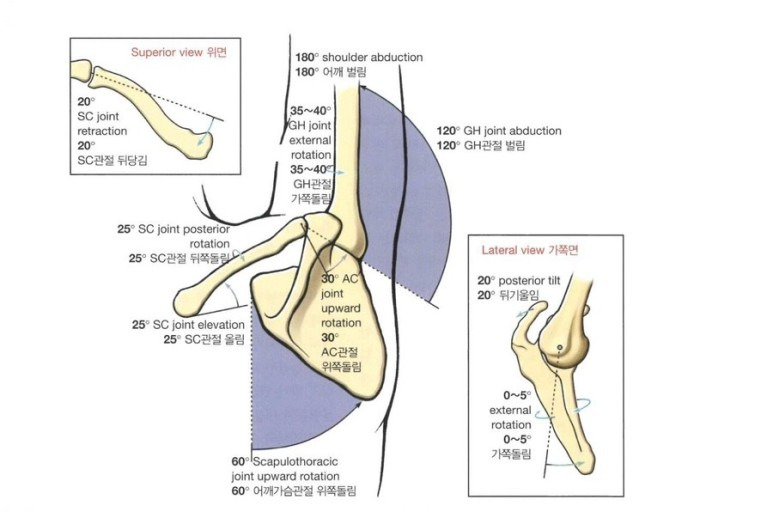

어깨가슴관절에서의

움직임은 다른 관절들과 협동에 의해 일어나고,

큰 움직임을 가지고 있기 때문에

어깨가 넓은 가동 범위를 가질 수 있게 됩니다.

어깨뼈와 가슴 사이에서 움직임도 일어나지만

대부분 복장빗장관절(SC)과

봉우리빗장관절(AC)의 협동에 의해 일어나고,

움직임이 더 잘 일어날 수 있도록 보조해 주는 역할을 합니다.

이 관절들 중 한 관절에서라도 움직임의 제한이 생긴다면

어깨뼈의 움직임을 제한하게 되고

추후엔 어깨의 움직임 자체를 제한하게 됩니다!

어깨가슴관절에서의 위쪽 돌림은

어깨를 완전 벌림 또는 완전굽힘시에 중요한 역할을 합니다!

어깨의 완전 벌림동안

복장빗장관절(SC)은 올림이 일어나고

봉우리빗장관절(AC)은 위쪽 돌림이 일어납니다.

완전벌림 시

어깨가슴관절에서 약 60도 정도의 위쪽 돌림이 일어나야

정상 범위인 180도까지 올릴 수 있습니다.

아래쪽 돌림은 위쪽 돌림과 반대로 일어나며

빗장뼈의 내림, 어깨뼈의 아래쪽 돌림을 통해 제자리로 돌아옵니다.